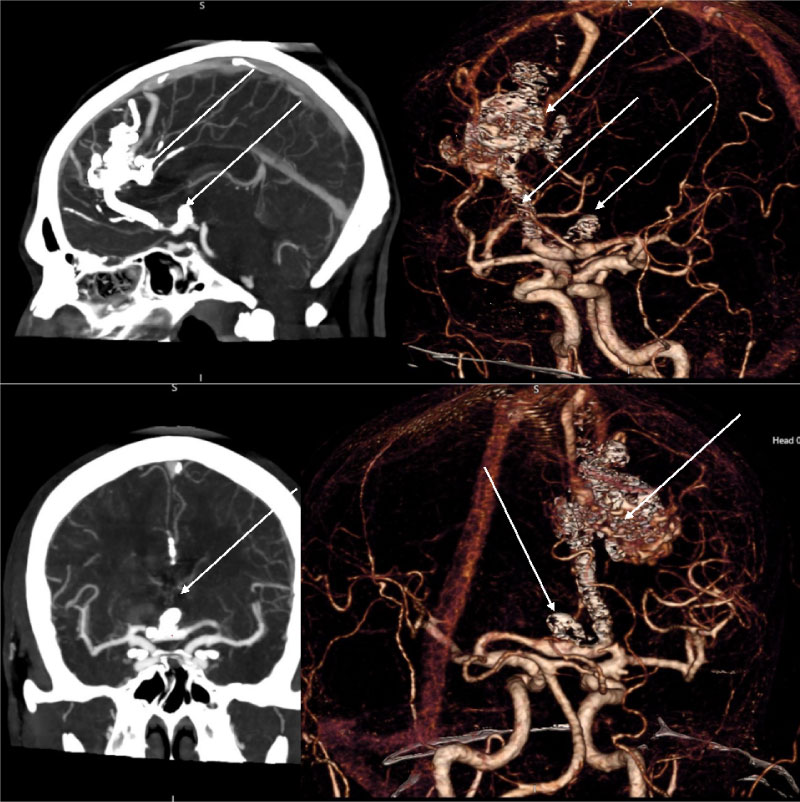

In order to determine the tactics of treatment, CT scan - angiography (Figure 1A) with cerebral vascular perfusion (Figure 1B) and selective cerebral angiography (Figure 1C) were performed. An arteriovenous malformation of the fronto-parietal region (Spetzler-Martin 4) was detected with proximal flow-related aneurysm of the right anterior cerebral artery measuring 11.5 × 7.0 × 6.0 mm with the neck size 5.0 mm.

Figure 1: CT - angiography, CT - perfusion and cerebral angiography before endovascular treatment. 1A) CT - angiogram showing AVM and aneurism localization; 1B) CT - prefusion showing hyperperfusion zone in AVM and high-flow drainage vein; 1C) Cerebral angiography showing AVM of the right fronto-parietal region and the proximal flow - related aneurysm on the right terminal ACA afferent. View Figure 1